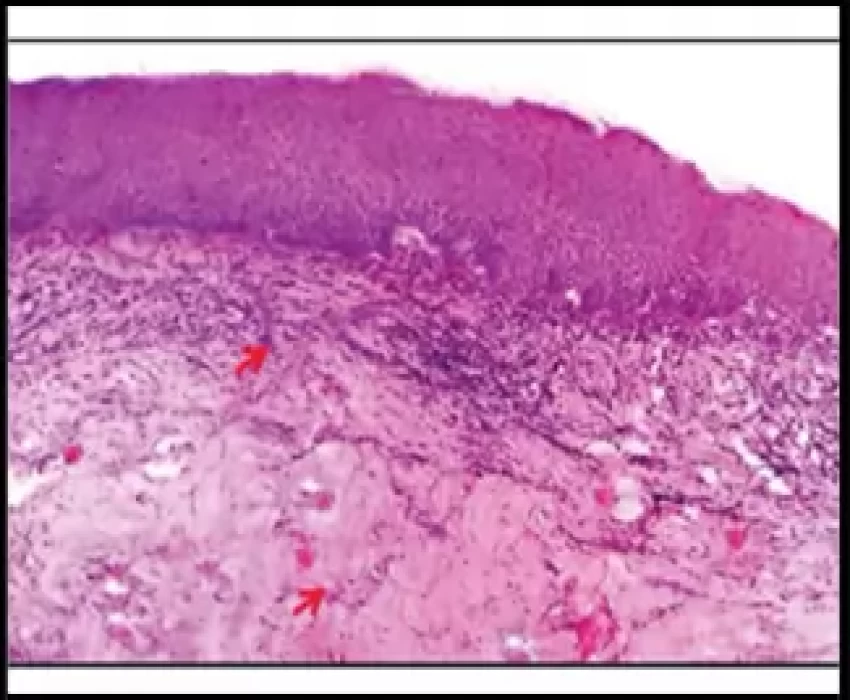

Oral Submucous Fibrosis (OSMF) is a precancerous condition and is mainly associated with the chewing of areca nut. This study was undertaken to correlate the etiological factors (duration, frequency, style and chewing habit) associated with OSMF with clinical grading and histological staging. The widespread habit of chewing gutkha plays a major role in the development of Oral Submucous Fibrosis than any other habit. The duration and frequency of its use and type of areca nut product has effect on the incidence and severity of OSMF.

The widespread habit of chewing gutkha has major role in the occurrence and severity of OSMF, especially in younger age group. The occurrence of OSMF in gutkha chewers is faster and more severe as compared to any other forms of areca nut products. The relative risk of disease increased with frequency and manner of chewing which conclude that the daily consumption rate appears to be relatively significant with respect to risk than the lifelong duration of habit. The histological grade should be considered as the gold standard in deciding the treatment plan and routine surveillance programme should be carried out in order to stop this perilous habit.